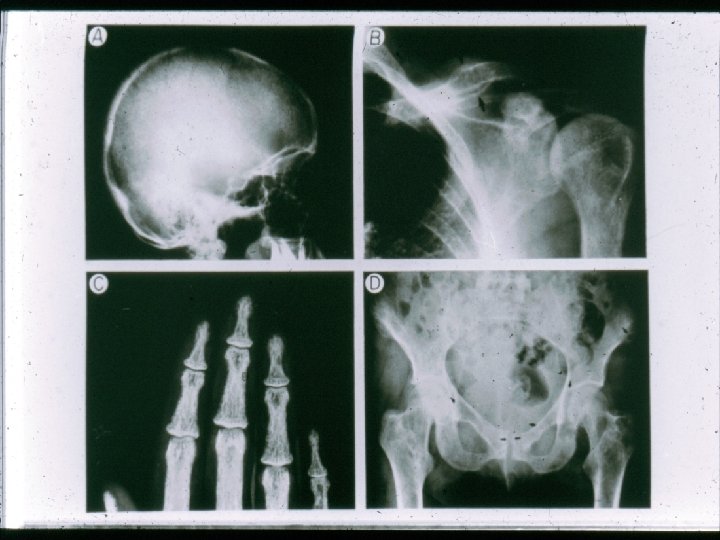

ΚΛΙΝΙΚΕΣ ΕΚΔΗΛΩΣΕΙΣ ΠΡΩΤΟΓΕΝΟΥΣ ΥΠΕΡΠΑΡΑΘΥΡΕΟΕΙΔΙΣΜΟΥ 1. Asymptomatic hypercalcemia detected by routine biochemical screening 2. Symptomatic hypercalcemia 3. During evaluation for manifestations of hyperparathyroidism such as osteopenia, osteoporosis, or nephrolithiasis 4. Rarely, hyperparathyroid bone disease (osteitis fibrosa cystica) or parathyroid crisis

Symptoms and signs of excess parathyroid hormone secretion • • • Symptoms and signs of hypercalcemia Bone disease Nephrolithiasis Hypophosphatemia Increased production of calcitriol Proximal renal tubular acidosis Hypomagnesemia Hyperuricemia and gout Anemia

Η ΜΟΝΤΕΡΝΑ ΚΛΙΝΙΚΗ ΕΙΚΟΝΑ ΤΟΥ ΠΡΩΤΟΓΕΝΟΥΣ ΥΠΕΡΠΑΡΑΘΥΡΕΟΕΙΔΙΣΜΟΥ Cope et al. 19301965 Nεφρολιθίαση Heath et al. Mallette et 1965 -1974 al. 1965 -1974 Silverberg, Bilezikian et al. 1984 -2006 57% 51% 37% 17% Not reported 36% 40% 39% Εμφανής σκελετική νόσος 23% 10% 14% 1. 4% Ασυμπτωματικός 0. 6% 18% 22% 80% Υπερασβεστιουρία Silverberg SJ and Bilezikian JP (2006)

Η βιοχημική εικόνα του πρωτογενούς υπερπαραθυρεοειδισμού στην μοντέρνα εποχή Παράμετρος Τιμές Ασθενείς Φυσιολο. • Calcium (mg/dl) 10. 7± 0. 1 8. 4 -10. 2 • Phosphorus (mg/dl) • Alk Phos (IU/l) 2. 9± 0. 1 114± 4 2. 5 -4. 5 <100 • PTH (pg/ml) 121± 7 10 -65 • • 21± 1 59± 2 248 + 12 17 + 6 9 -52 15 -60 100 -300 4 -21 25 -OH Vit D (ng/ml) 1, 25 -OH 2 Vit D (pg/ml) Urinary calcium (mg) DPD (nmol/mmol Cr) Silverberg, Bilezikian et al.

Bone Mineral Density: % of Expected Η οστεοπυκνομετρική εικόνα του πρωτογενούς υπερπαραθυρεοειδισμού στην μοντέρνα εποχή 100 * * * Differs from ra p<. 05 90 80 70 Lumbar Spine Silverberg, Bilezikian et al. JBMR, 1989 Femoral Neck Radius